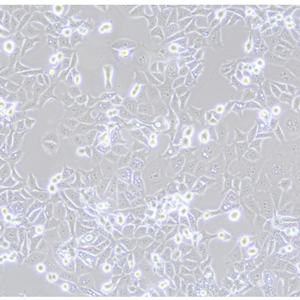

KYSE-30(人食管鳞癌细胞)